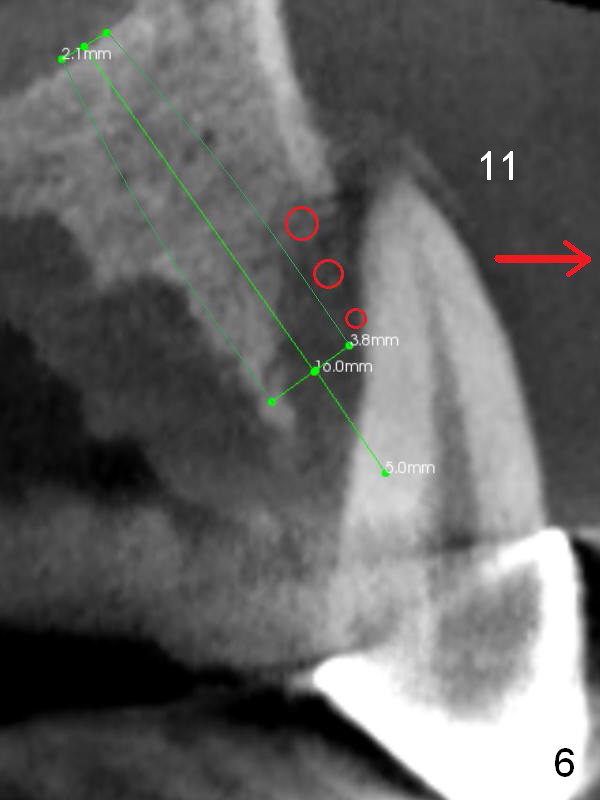

Alginate impression will most likely dislodge #11-15 loose FPD. Start osteotomy at #11 and 15 first (Fig.6, 10) and use the teeth #9 and 10 as trajectory reference. Prepare PRF (Fig.10 white curved line) and Magic Lifter for #15.

In case primary stability is questionable for example at #15 (Fig.10), consider placing implants at #12 and/or 14 (Fig.7,9).